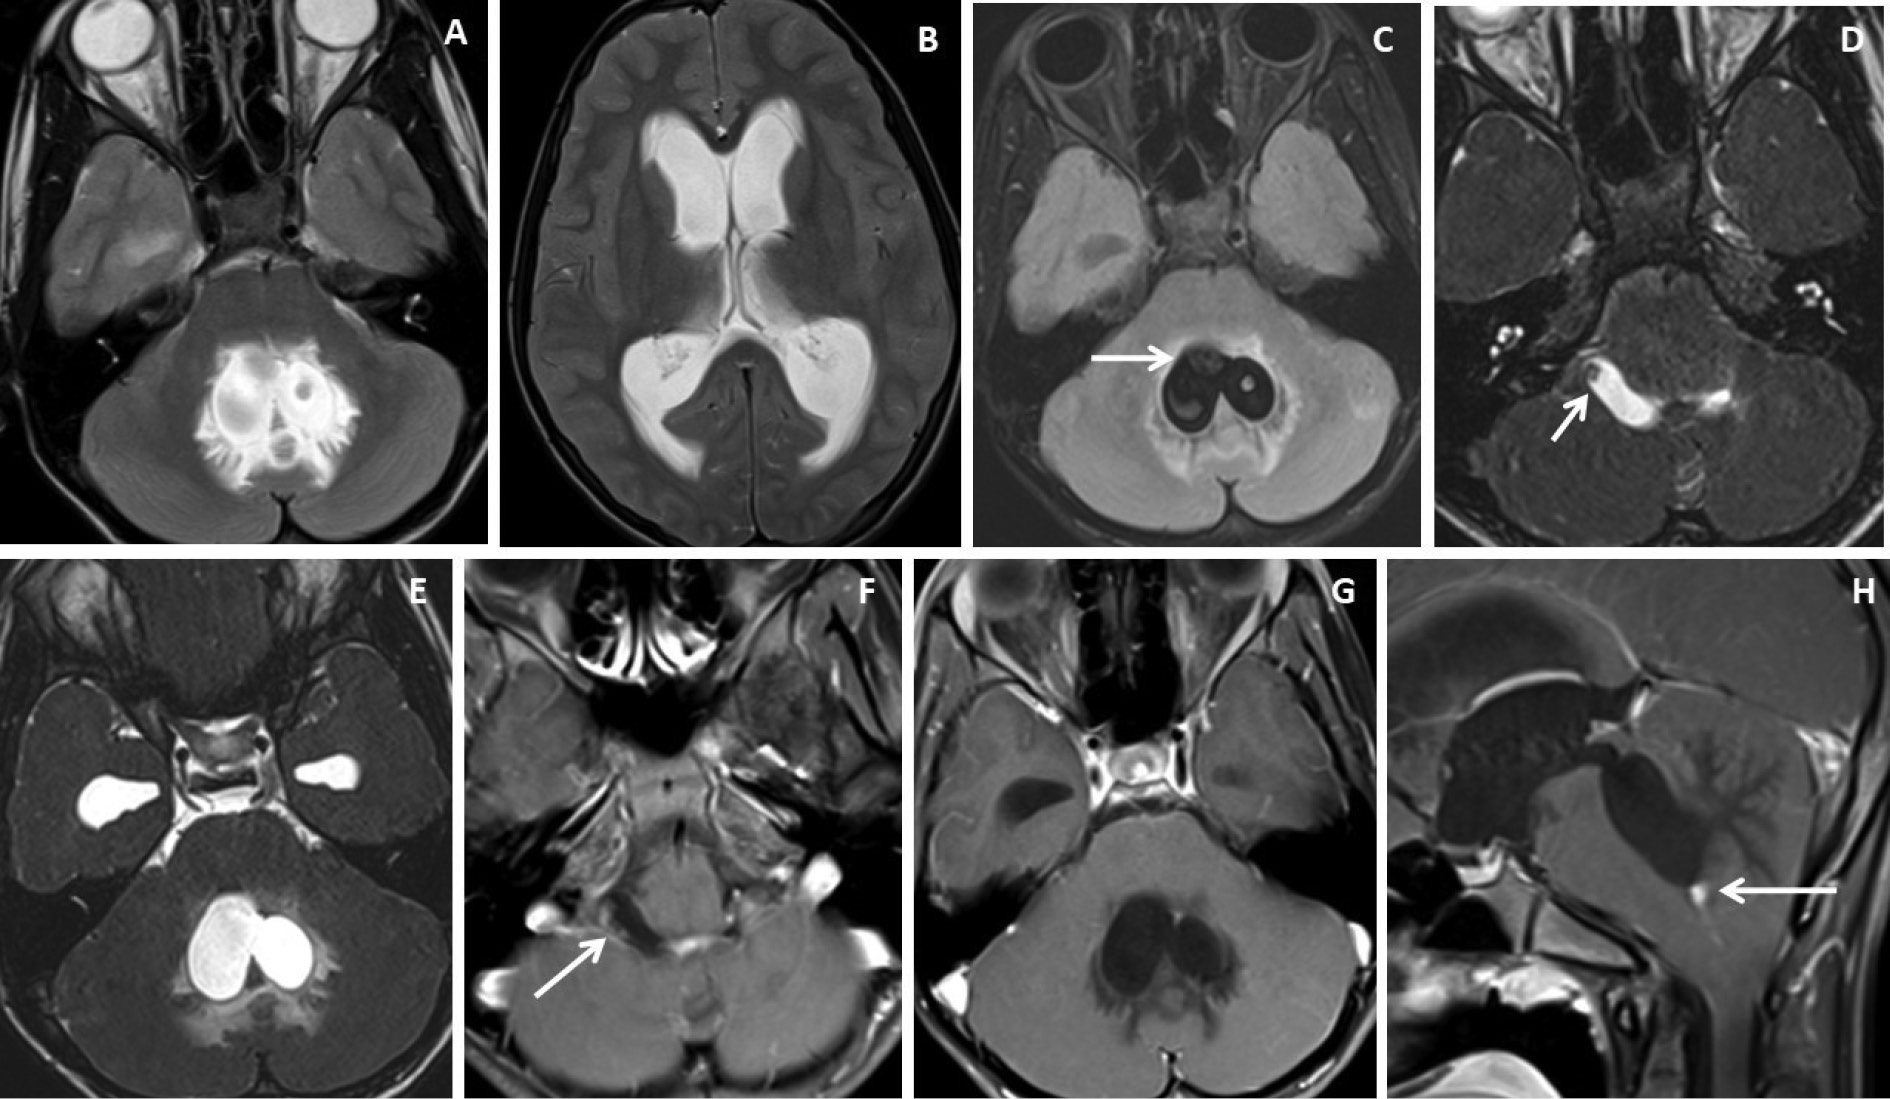

Figure 4. Brain magnetic resonance imaging of 13 years male with severe headache, vomiting and acute neurological deterioration. (A-B) Axial T2WI images show marked distension and dilatation of the fourth ventricle with marked periventricular CSF seepage and supratentorial hydrocephalus. (C) Axial FLAIR image shows cystic lesions within the fourth ventricle (arrow). (D-E) Axial heavily T2W images show thin-walled hyperintense cystic lesions within the 4th ventricle with an oval to elongated appearing cystic lesion with scolex in the right foramen of Luschka (arrow). (F-H) Axial and sagittal T1W post-contrast image shows a thin peripheral enhancing cystic lesion with an irregular mural nodule in the right foramen of Luschka (arrow) and thin smooth enhancement of the intraventricular cysts. Nodular enhancement was seen in midline inferior margin of 4th ventricle near to foramen of Magendie (arrow).

Figure 3. Brain magnetic resonance imaging of 25 years male with headache. (A-B) Axial T2WI and FLAIR images show distension and dilatation of the fourth ventricle with minimal periventricular CSF seepage. Variable signal intensity cystic lesions are seen within the fourth ventricle on the FLAIR image (arrow). (C-D) Axial and coronal heavily T2W images show multiple thin-walled hyperintense cystic lesions (arrows) with less hyperintense CSF signal within the 4th ventricle with variable sizes irregular nodules within. (E-F) Axial and sagittal T1W post-contrast image shows thin smooth enhancement of the intraventricular cyst (arrow) with enhancing irregular nodules. Post-contrast enhancement is also seen along the ependymal lining of the 4th ventricle, in posterior and inferior aspects.